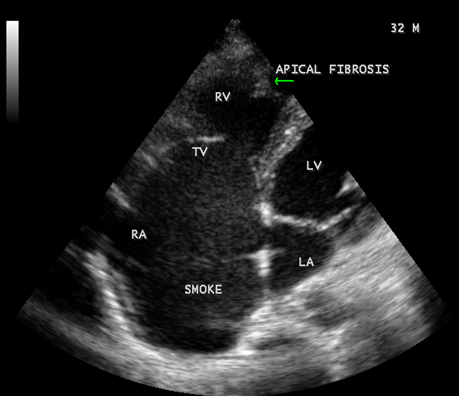

Figure 36: Endomyocardial fibrosis showing SEC (spontaneous echo contrast or smoke) in the right atrium in a 32 -year old male.

When the endocardium is replaced by collagenous fibrosis (consist of collagen deposition and fibroblast proliferation), the final fibrotic stage is reached after several years of disease activity. Fibrotic obliteration of the apices of the affected ventricles is the hallmark of the disorder and fibrosis involving the papillary muscles and chordae tendineae leading to atrioventricular valve distortion and regurgitation. In the left ventricle, the fibrosis extends from the apex to the posterior mitral leaflet, usually sparing the anterior mitral leaflet and outflow tract and cause PML (posterior mitral leaflet) distortion and regurgitation. Like the peculiar geographical distribution, the fibrotic endomyocardial involvement stops short of the ventricular outflow tract like a ridge [17] as shown in Figures 15,29,31,35 and 44. The fibrotic tissue often creates a nidus for thrombus formation, which can be extensive. Atrial thrombi also occur and the right atrium may be aneurysmally dilated. Aneurysmal right atrium with spontaneous echo contrast was detected in a 32- year old male as shown in Figure 36 [18- Figure 3]. In addition, there are fibrosis and granular septation extending into the underlying myocardial tissue and myocyte hypertrophy is common [19]. Fibrotic process causes tethering of leaflets into ventricular walls and may mimic Ebstein’s malformation as shown in Figure 38[20],[21]. Fibrosis increases the stiffness of the heart, resulting restrictive physiology, AV (atrioventricular) valve regurgitation which has been linked to atrial arrhythmias such as atrial fibrillation as shown in Figures 19 and 20 in a 62-year old female. Atrial fibrillation has been reported in more than 30% of patients with EMF. Fibrosis impairs activation patterns of the conduction system and may provide substrate for wave breaks and reentry [22]. Fibrosis reduces conduction velocity and cause conduction abnormalities like junctional rhythms, heart blocks as shown in Figure 21 and 22 in a 75-year old female and atrioventricular conduction delay [23].

Today echocardiography is used as the screening tool at the community level as the diagnosis of EMF could be confirmed at the bedside. Echocardiography accurately assesses the pathological abnormalities of chronic disease and it is the gold standard technique for the diagnosis of EMF [36]. It reveals dense endomyocardial echocardiograms along different parts of the mural and valvular endocardium and AV valve dysfunction [37] as shown in Figures 3 to 44. The typical feature of EMF is the obliteration of trabecular portion of the ventricle and in advanced cases, there is shrinkage of the cavities creating an apical notch, regurgitation, slow flow with spontaneous echo contrast as in Figure 36 and considerable pericardial effusion. Similar to apical notch of right ventricle, a right atrial notch is well seen as contraction (or retraction) of tricuspid annulus as in Figure 40 and right atrial notch as in Figure 41 and 42, indicating the retraction of rightatrial cavity as a peculiar feature of right ventricular EMF. Biventricular enlargement as shown in Figure 40 and biatrial enlargement as in Figure 32 are the characteristic features of advanced stage of EMF. The fibrosed muscular trabeculae extending into the cavities from the walls of the chambers in the right ventricle visible as ‘cobra heads’ as in Figure 4 and in pericardial sac as in Figure 29, in the left ventricle. Aneurysmal right ventricle with scattered areas of fibrosis in the sub tricuspid region and a notch in the right atrium is well seen in a 14 –year old boy as in Figure 42 . Right atrial notch is frequently noticed in EMF patients as shown in Figure 41 in a 47- year old male with left ventricular EMF and moderate pericardial effusion.